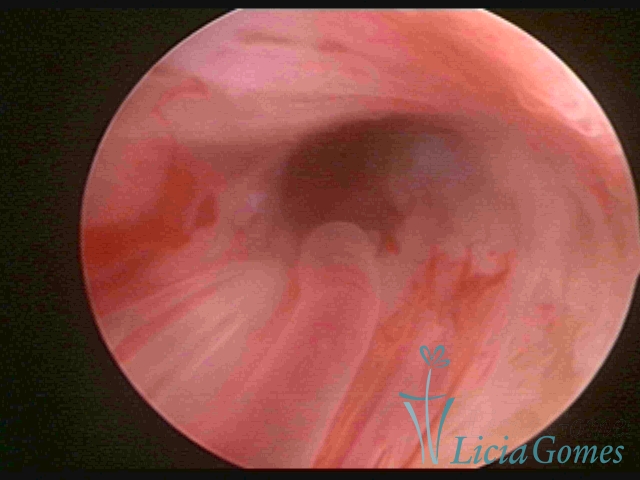

PÓLIPOS ENDOCERVICAIS

São tumores benignos, resultantes da proliferação focal reativa aos processos inflamatórios ou à situações de hiperestrogenismo, e podem ter sésseis (com a base de implantação larga) ou pediculados do epitélio.